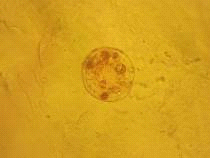

.2.2 Микроскопический анализ

Важным диагностическим признаком являются

рассеянные по всей поверхности листа многочисленные сосочковидные и

конусовидные волоски с бородавчатой поверхностью (рис. 13). На нижней стороне

листа в небольших углублениях расположены эфирномасличные железки, состоящие из

8 радиально расположенных клеток и одноклеточной короткой ножки. [1]

Рис. 13. Многоклеточные волоски листа мелиссы